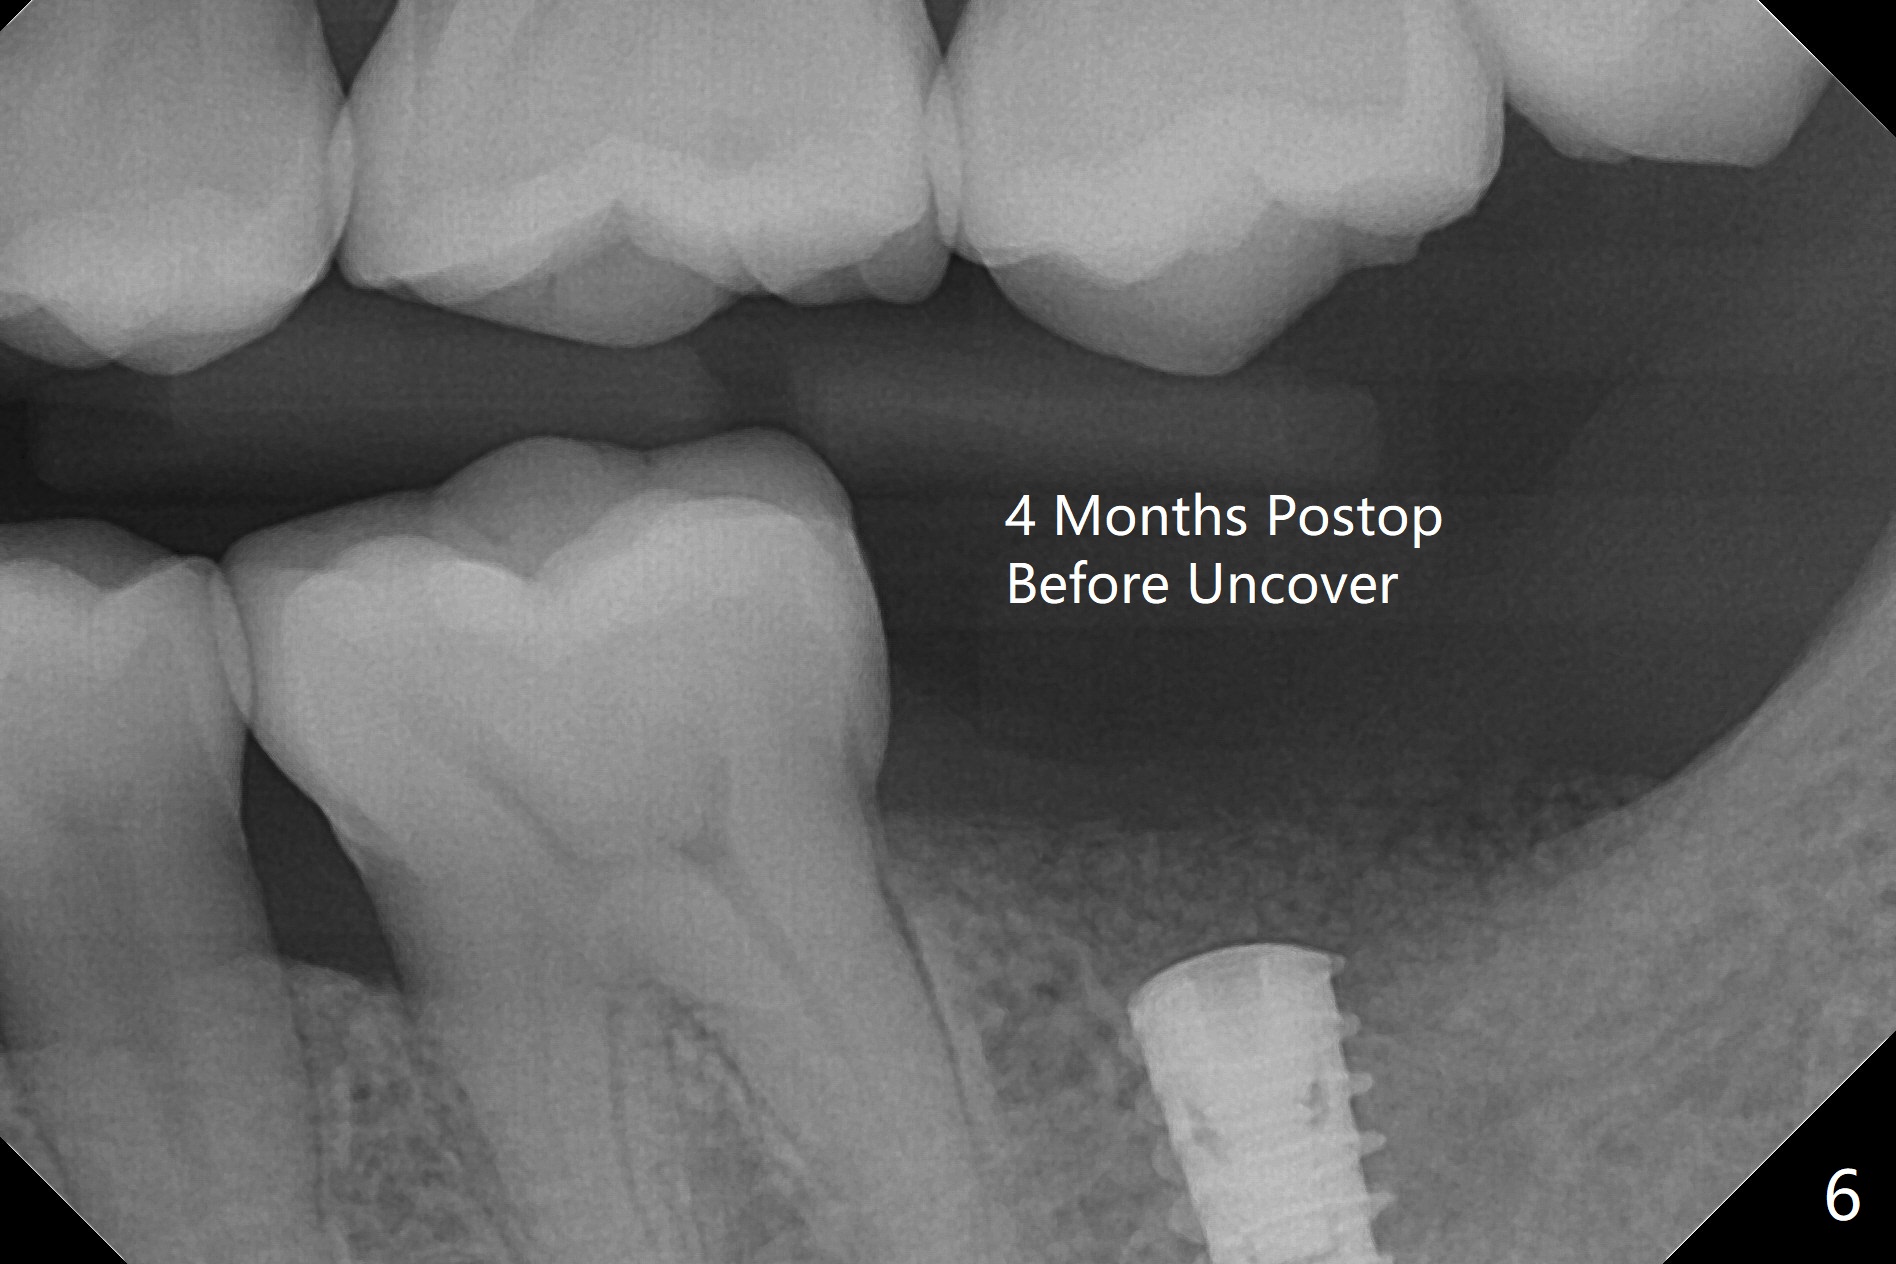

左下7钻洞中出现三种情况:容易出血(血小板减低(9万)),疼痛(根尖肉芽肿)和骨质疏松,钻洞深度还没达到,使用短小报废植体拍摄根尖片(图一),之后下颌牙槽神经阻断,钻洞没有疼痛,但是未注意骨质疏松问题,按照正常钻洞顺序,所以正式植体扭力低,10 Ncm(图二),放置骨粉和不可吸收膜,PTFE缝合(图三)。术后一周膜舌侧稍微外翻(剪太小些,图四)。病人将术后五周回来去除膜,之后拍摄咬翼片证实骨粉丧失与否。其实病人提前回来,抱怨缝线不适,膜不翼而飞(图五,折线后),患侧咀嚼,因为对侧下颌第二磨牙疼痛又不肯拔除。The bone graft placed at the time of immediate implant (Fig.3 *) is apparently changing into the normal bone 4 months postop before uncover (Fig.6). After removal of the bone coronal to the implant with a curette, a 4x4(3) mm pair abutment is placed (Fig.7). Two weeks later the abutment screw is torqued at 20 Ncm.